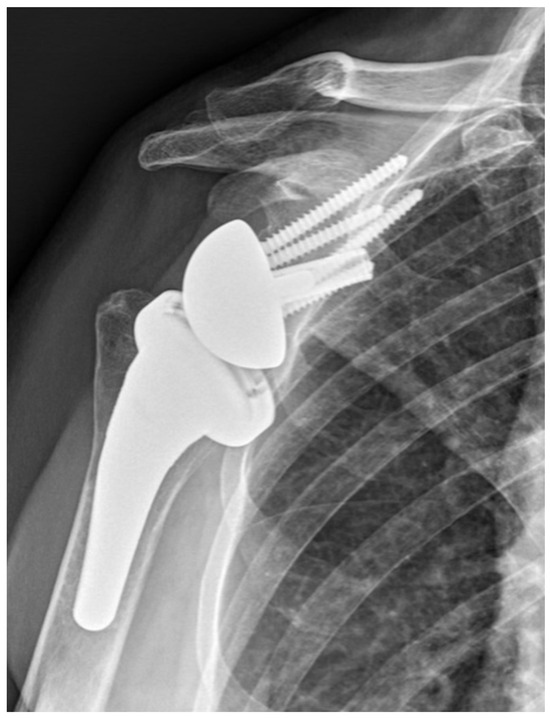

2.2. Surgical Procedure